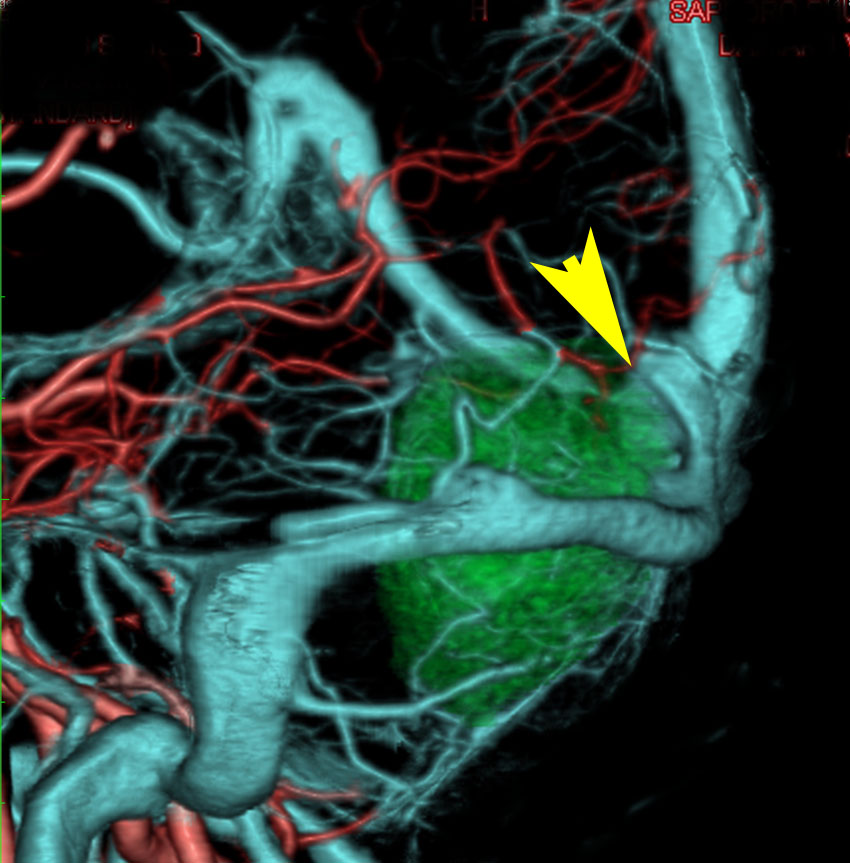

軽度の閉塞性水頭症もありますが,頭痛も無く無症状なので経過を観察しました。髄膜腫だと診断できるのは,右の画像で見られるようにガレン大静脈が右側に偏っているからです。松果体細胞腫の場合は,ガレン大静脈は上方に変位します。

1年間経過観察したら水頭症が進行して脳室が拡大,腫瘍のサイズも大きくなりました。右側の画像で見られるようにガレン大静脈の左側のテントの下面から発生した髄膜腫でした。